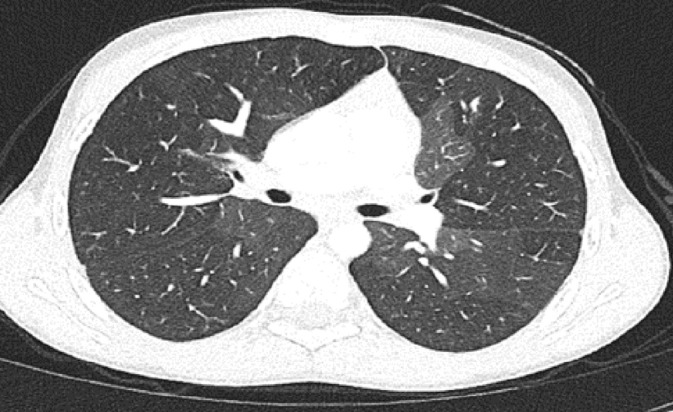

Results: Sixteen patients were enrolled. Median age at diagnosis was 27.5 months (range: 7-195 months). Wheezing was the most common presenting symptom. The most prevalent finding on thoracic CT was a mosaic pattern. In all but one, a wide range of variations genes related to both pulmonary structure and function were identified. The genes identified included those related to primary ciliary dyskinesia (DNAH genes), surfactant metabolism disorder (ABCA3, CSF2RB), pulmonary fibrosis (MUC5B, SFTP), and bronchiectasis (SCNN1B).